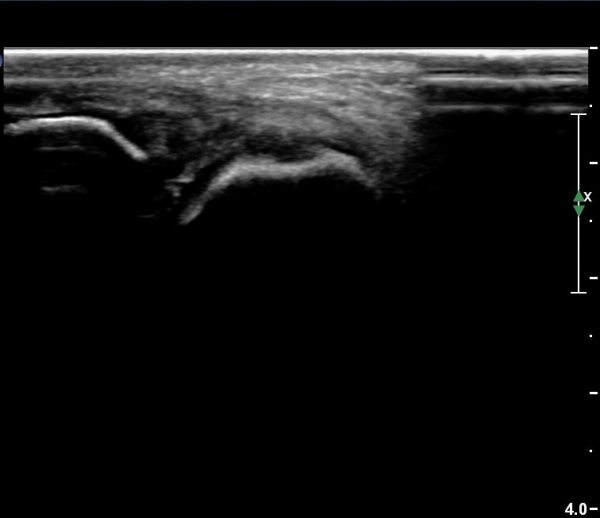

Àü¹æ °æ°ñºñ°ñÀδë Á¾´Ü¸é°Ë»ç¿¡¼­ ƯÀÌ ¼Ò°ßÀ» º¸ÀÌÁö ¾Ê´Â´Ù(»çÁø 3).

¹ß¸ñ°üÀý ¾ÕÂÊ Á¾´Ü¸é°Ë»ç¿¡¼­ °üÀý³» ¼ö¾×Àú·ù°¡ »ç¶óÁö°í(»çÁø 1),